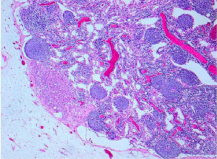

He had distal pancreatectomy and splenectomy. His histology showed normal tubular and acinar morphology within a vascular stroma. There was modest nuclear pleomorphism with some chromatin aggregation, prominent nucleoli and abundant granular cytoplasm (Figure 5).

Figure 5 Tumor in high power modest nuclear pleomorphisim, prominent nuclei with abundant granular cytoplasm.